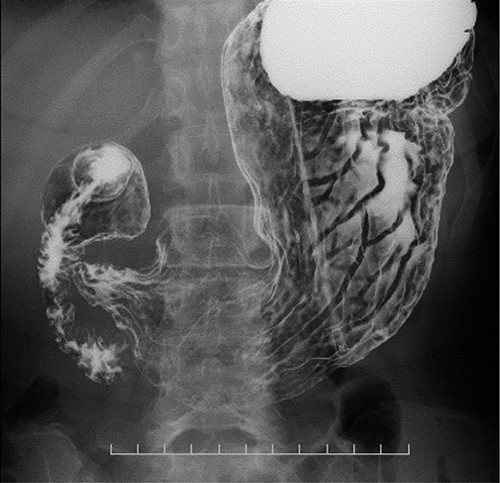

Coronal plane of the CT findings; CT demonstrates dilatation of the upper thoracic esophagus.

Preoperative computed tomography (CT) and barium meal studies were performed. The CT findings showed circumferential wall thickening with infiltrative change at the middle of the intrathoracic esophagus, with luminal dilation of the oral side of the stenotic esophagus (Figs 2, 3). The barium meal study showed no abnormal findings in the stomach (Fig. 4). Thoracoscopic esophagectomy was performed with the patient in the semi-prone position, followed by esophageal reconstruction using a gastric tube with the patient in the supine position. The operation was started with bilateral lung ventilation using a single-lumen endotracheal tube. A four-port thoracoscopic technique was used as follows: an observation port with a 10-mm scope was placed at the ninth intercostal space at the line of the inferior scapular angle, and two 5-mm ports and one 12-mm port for the intrathoracic procedures were placed at the third, fifth and seventh intercostal spaces, respectively, at the posterior axillary line (Fig. 5). Pneumothorax was created using 10 mmHg of CO2 to deflate the lung to achieve a better operative field. The pleura and connective tissue around the thoracic esophagus showed severe inflammatory and fibrotic changes. In particular, the middle thoracic esophagus was strongly adherent to the arch of the azygos vein and the tracheal bifurcation.